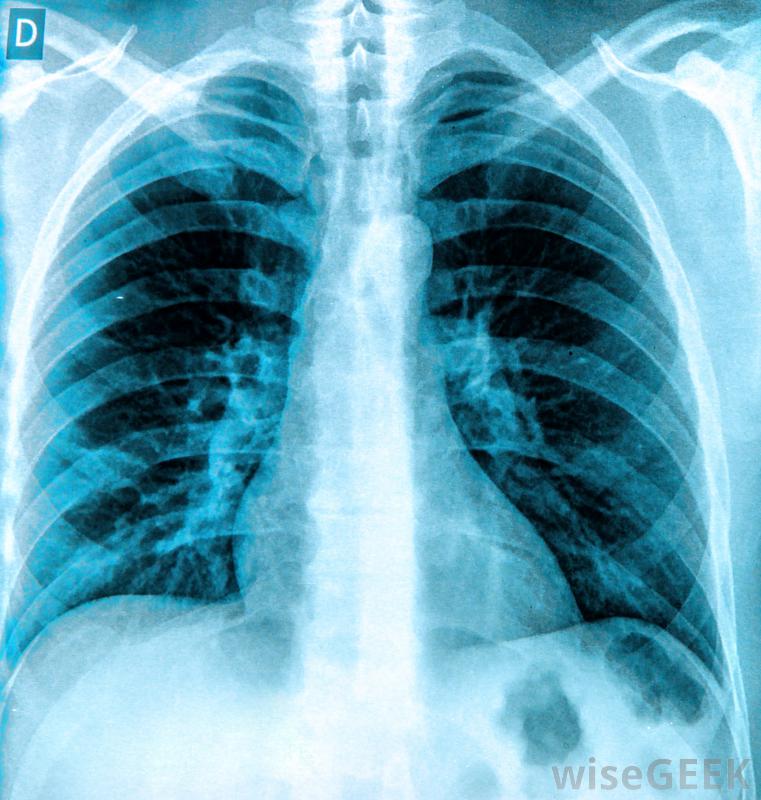

癌症、创伤,感染是胸腔积液的可能原因。癌症、外伤和感染都是渗出性胸腔积液的可能原因。在所有这些病例中,局部的细胞损伤会迫使细胞泄漏蛋白质和其他物质。虽然胸膜腔通常有一些液体来润滑肺部,但当太多液体积聚时,很难呼吸。胸部的一侧或两侧可能受累,患者通常会出现呼吸困难、奇怪的呼吸音和问题像紫绀一样,由于氧合不足,四肢开始发蓝。

可以通过X光来诊断胸腔积液医生可以插入针头或引流管来迅速缓解积液液体的样本可以被带到实验室进行分析,以了解体内发生的情况。如果是渗出性胸腔积液,那么这些样本中的蛋白质水平会很高。蛋白质和其他物质的平衡也可以为胸腔积液的病因提供线索,就像恶性胸腔积液一样渗出性胸腔积液的症状可能包括呼吸困难渗出性胸腔积液的治疗首先要排出多余的液体,这样病人就可以更容易地呼吸了。一旦病人病情稳定,就可以开始对病因进行评估和治疗。治疗方案可以包括抗生素等治疗感染,以及治疗肺部及周围的癌性肿瘤。在诊断过程中,医生可能会召集专家来咨询,因为在诊断过程中会收集到更多关于积液的信息。